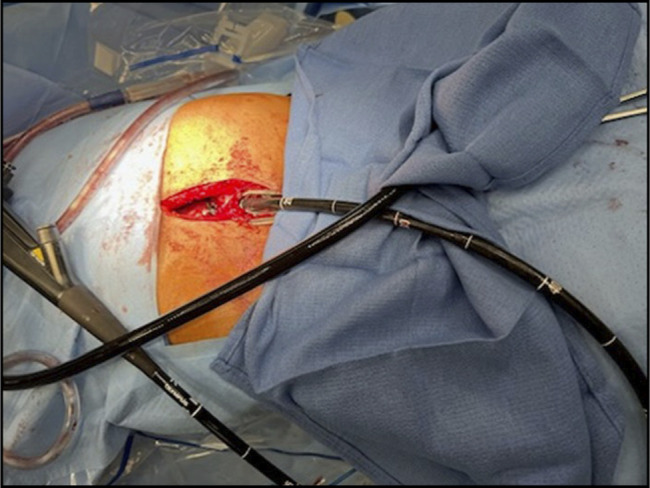

The combined antegrade and retrograde endoscopic rendezvous technique effectively restores patency for esophageal short-segment obstructing strictures (<3 cm). However, long-segment strictures typically require complex surgery, with endoscopic management rarely reported. We report a 44-year-old man with a 9 cm esophageal obstruction due to peptic stricture who was at high risk of esophageal resection due to severe cardiac disease and prior abdominal surgeries. He underwent successful recanalization using a rendezvous technique. Serial dilations with subsequent esophageal stenting restored luminal patency. This case highlights the feasibility of an endoscopic approach as a safe and effective alternative to surgery in long-segment peptic strictures.

Abstract Image